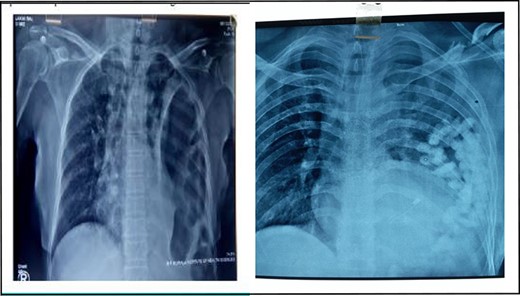

A retrospective analysis was carried out to review records of patients who presented to our department over a period of 3 years from December 2017 to January 2020. All patients with diaphragmatic hernias were included in the study. Preoperative diagnosis of diaphragmatic hernia was based on history, clinical examination and radiological investigations (chest X-ray and CT) (Figs 1 and 2).

X-ray chest showing collapsed left lung with herniated bowel loops in left thoracic cavity.